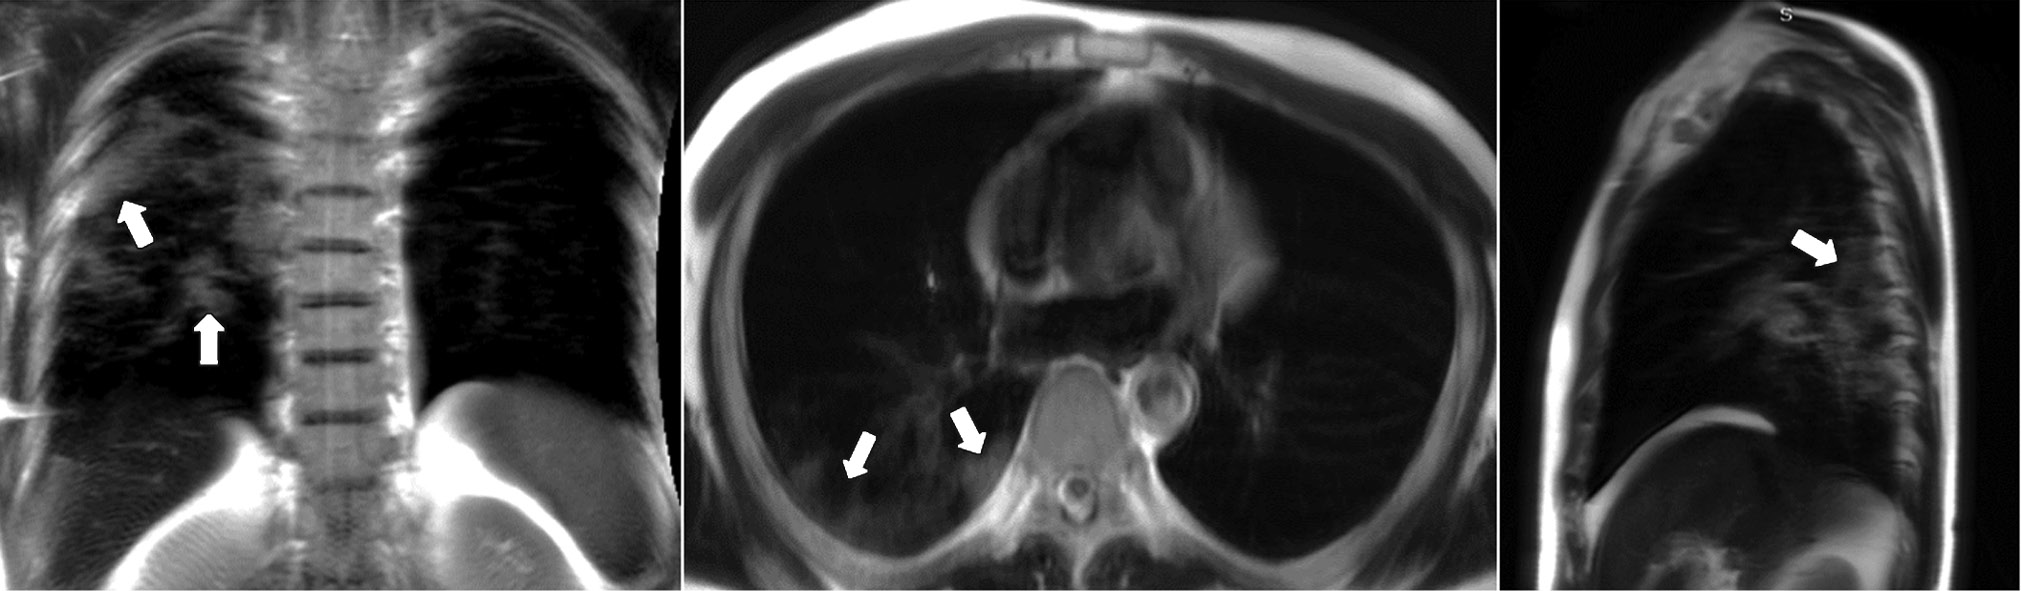

A patient (female, 45 years old) presented to the clinic on the fifth day after the onset of dry cough and mild fever up to 37.5°С. Dynamic lung MRI in the coronal plane (Fig. 1) showed an area of hyperintense signal in the lower lobe of the right lung (S9–S10), interpreted as an area of central induration (more intense signal) with a surrounding “cloudy sky” (less intense signal) during inhalation. A hyperintense signal was found in the corresponding area in the axial and sagittal planes, indicating consolidation with a “cloudy sky” along the edge of the area. At the end of exhalation, increased signal intensity was observed in the described area in the coronal plane (Fig. 2) with decreased visual size of the affected areas due to lung tissue contraction. During exhalation, no changes in signal intensity were observed in the axial and sagittal planes.

Figure 2. Dynamic magnetic resonance imaging of the lungs during exhalation in the coronal, axial, and sagittal planes. Arrows indicate the areas of consolidation (S9–S10).